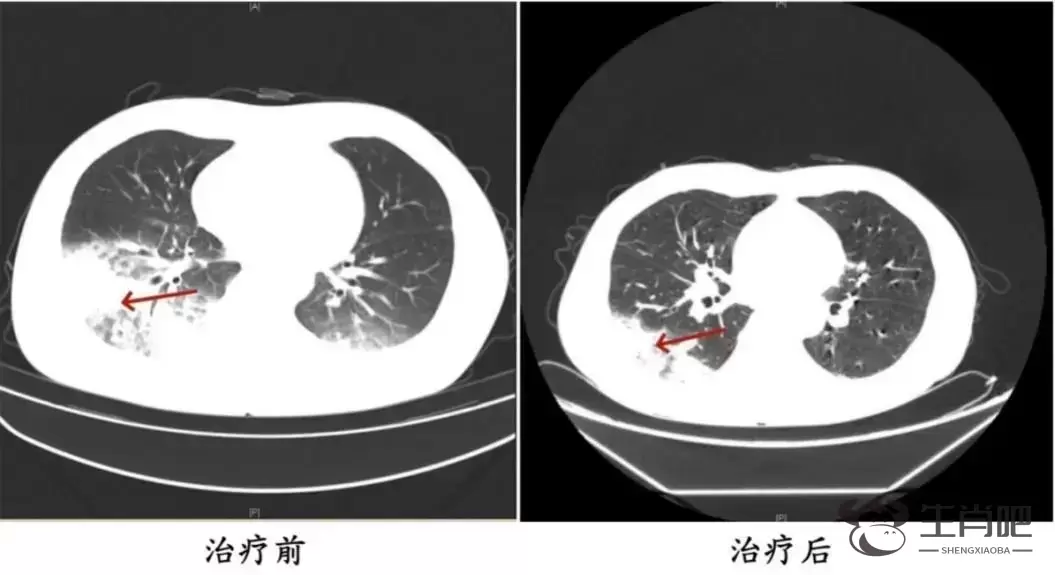

周先生治疗前后的肺部CT影像